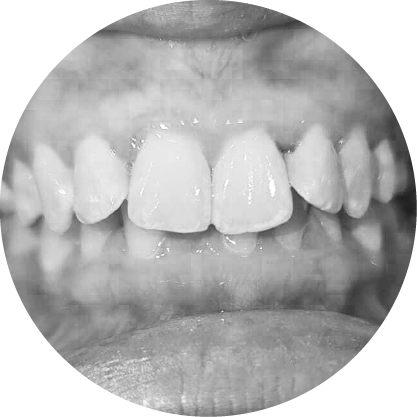

ตัวอย่างในชีวิตจริง